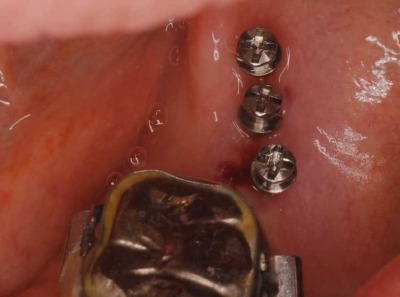

治療では、左下の奥歯に3本の矯正用インプラントを入れました。

拡大した写真です。

レントゲンで見ると分かりますが、結構小さいインプラントです。